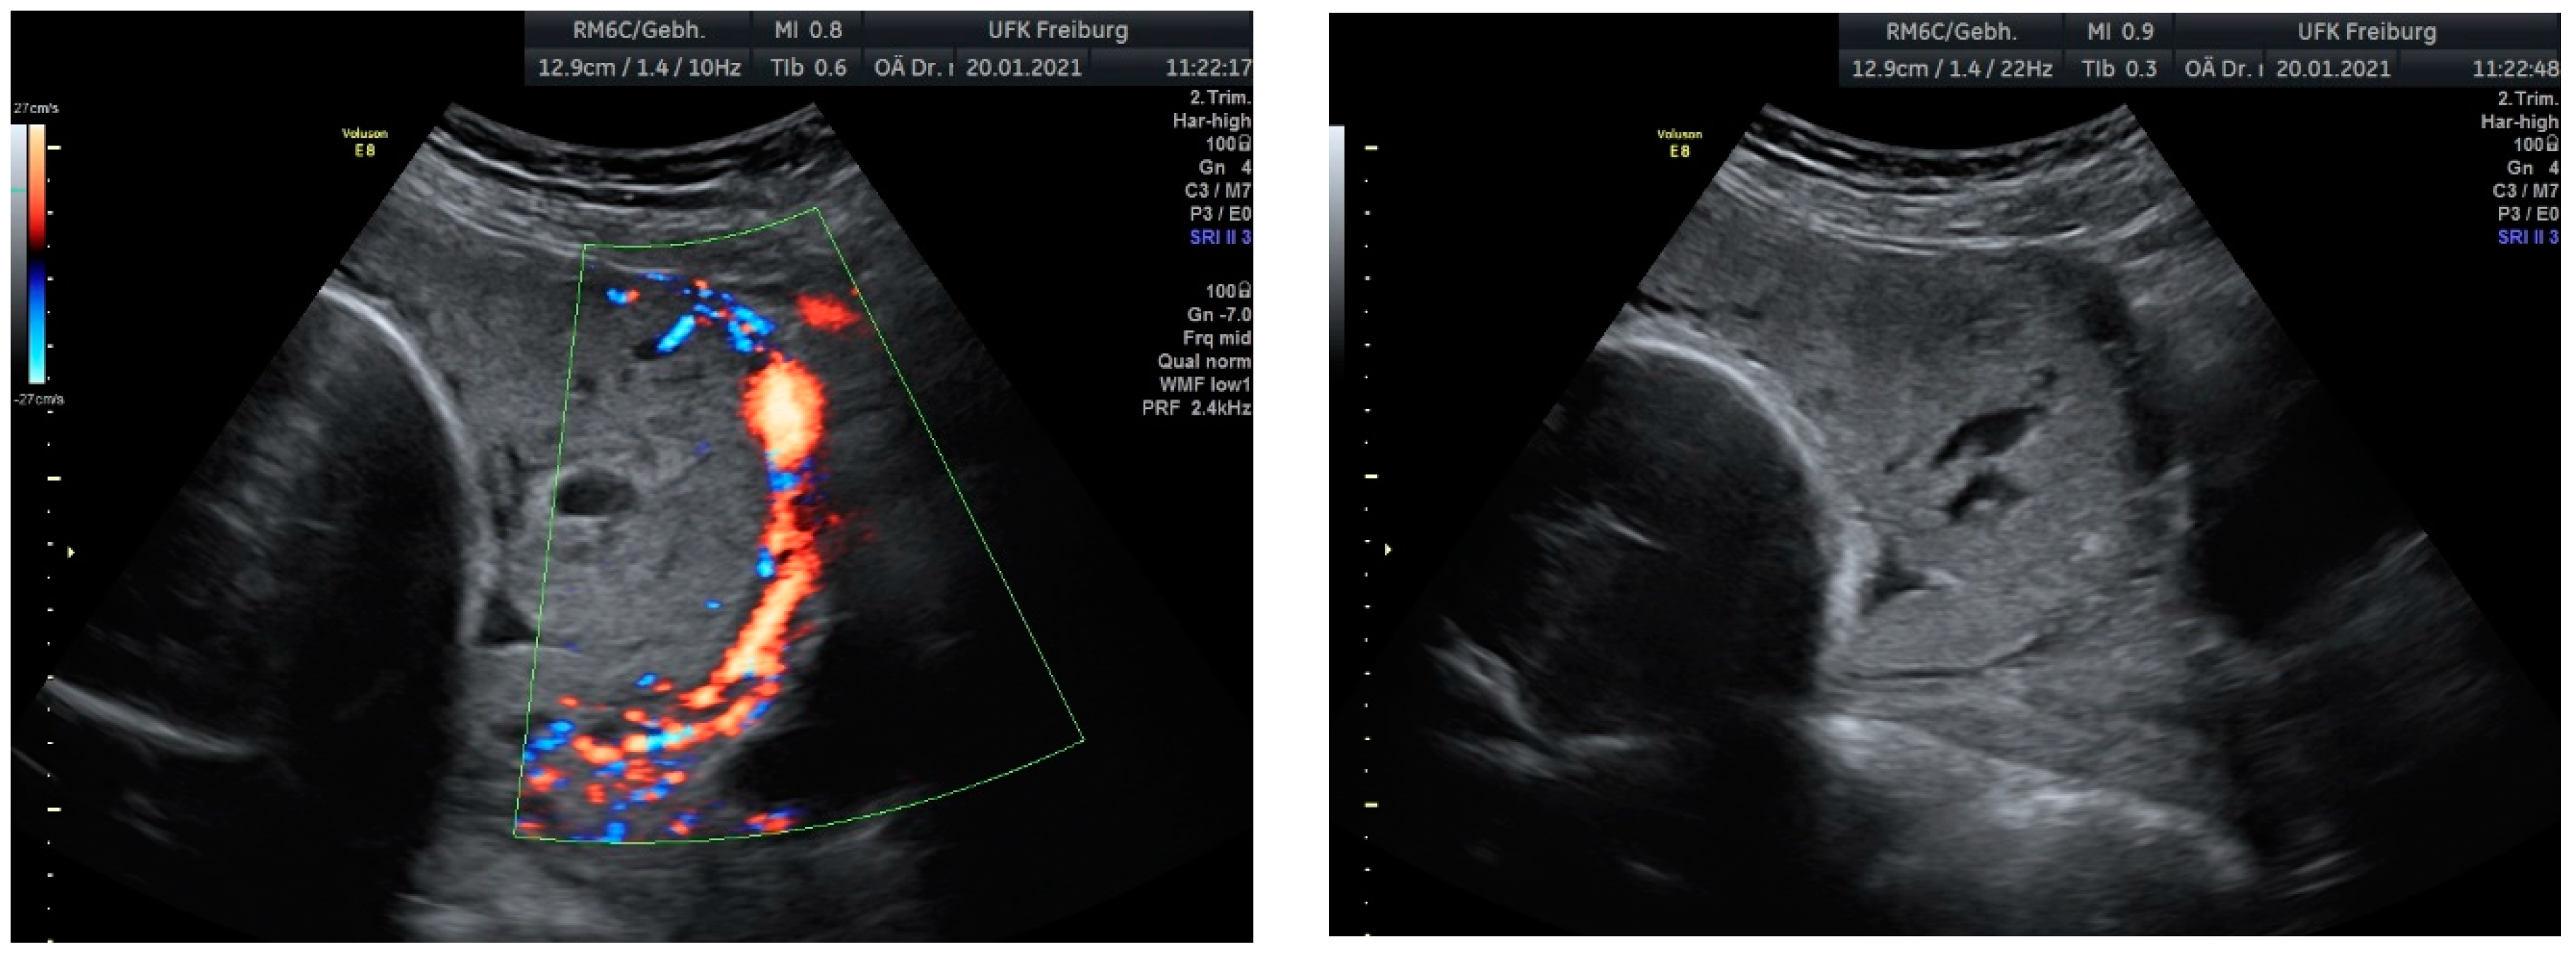

Sonographic findings (Figure 7):

Figure 7.

Revealed the following sonographic findings:

A very small barrier between the uterus and the bladder, with no recognizable

- myometrium in this area.

- Numerous blood vessels, most parallel and two perpendicular.

- Multiple placental lacunae confirmed by color Doppler.

Based on these findings, we planned an elective cesarean section at 35 weeks of gestation, combined with a hysterectomy due to the confirmed placenta increta and the high risk of significant bleeding. These findings were confirmed during the laparotomy.